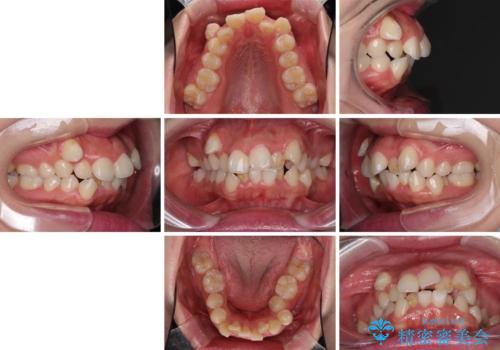

著しい叢生と顎骨のズレ ワイヤー装置による抜歯矯正

- 前歯の著しい叢生や八重歯を気にして来院された患者様です。

上下の顎がずれており、上下の正中は歯1本分の差がありました。

上下左右の小臼歯4本を抜歯し、極力正中を合わせるように矯正治療を始めていくこととしました。